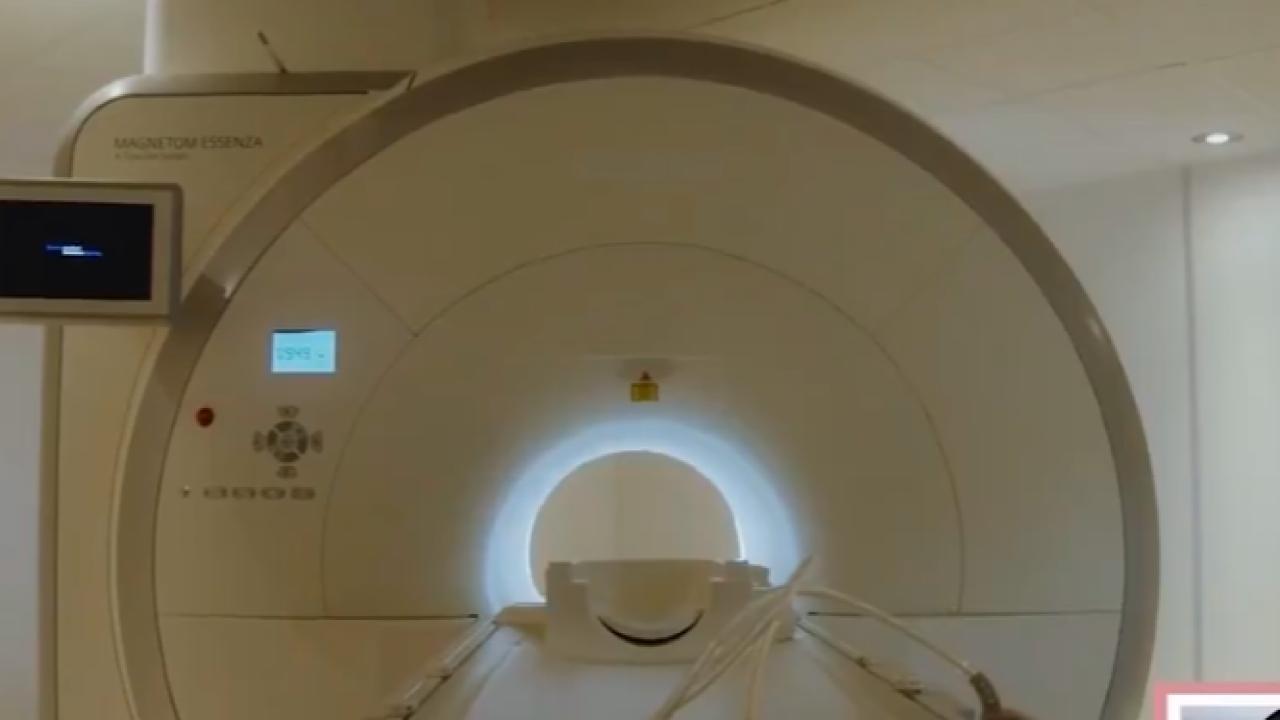

تجمع جازان الطبي يكتشف علاجاً فعالاً لسرطان الرئة.. فيديو

اكتشاف علاج يقلل من خطر الوفاة بسرطان الرئة